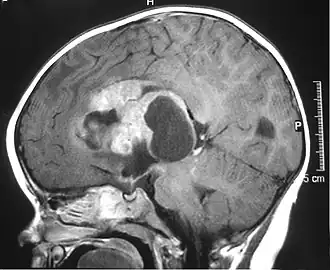

![]() Imagen de resonancia magnética de un tumor teratoideo/rabdoide atípico (ATRT) supratentorial en un niño. | ||

Los tumores rabdoides se dividen en tres según su localización inicial: renal, extrarrenal y del sistema nervioso central, este último se denomina tumor rabdoide teratoide atípico del sistema nervioso central y representa entre el 1 y el 2% de los tumores cerebrales en niños de menos de 3 años.